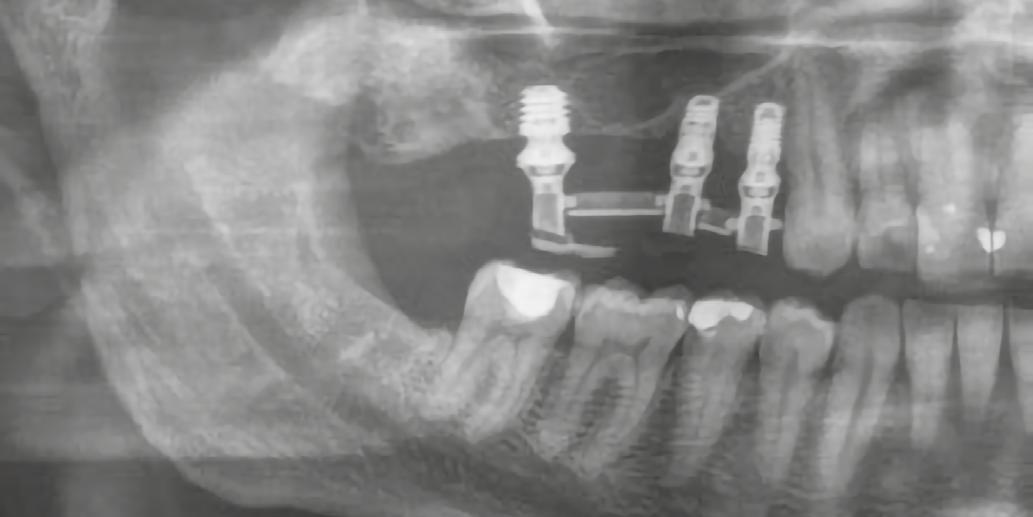

Kiindulási szituáció Egy 49 éves, nem dohányzó, egészséges férfi páciens jelentkezett a rendelőnkben hiányzó 2.6-os és 2.7-es foggal, valamint azzal a panasszal, hogy már lassan egy hete, lüktető fájdalmat érez a 2.5-ös fogánál. Megoldást keresett a hiányzó fogak pótlására is. Klinikai intraorális vizsgálat alapján a 2.5-ös fogon egy sérült fémkerámia korona volt,

1. ábra: Megfelelő szájhigiénia – panorámaröntgen. 2. ábra: A 2.5, 2.6 és 2.7-nek megfelelő terület a röntgenfelvételen.

és jelentős mobilitással rendelkezett. A radiológiai vizsgálat után egyértelműen látszódott, hogy a fogon még nem végeztek gyökérkezelést. A 2.6-os és 2.7-es fogaknak megfelelő területen az arcüreg kiterjedése jelentős volt, vertikális csontmennyiség szignifikánsan csökkent (1. és 2. ábra).

A 2.5-ös fog mentén periotómot haszáltunk, hogy átvágjuk a periodontális rostokat, így a fogat kilazítottuk, hogy ezzel is csökkenthessük a fogó által végzendő laterális mozgások szükségességét, illetve hogy a környező csontot is a legnagyobb mértékben megőrizzük. Nem volt elég csont (anélkül, hogy perforálnánk az arcüreg alapját) ahhoz, hogy abban stabilizáljuk az implantátumot, úgy döntöttünk, hogy behelyezünk egy ∅ 5.0 x 12 mm-es Straumann® BLX implantátumot közvetlenül az alveolusba, előfúrás nélkül. Az implantátum menetkialakítása lehetővé tette, hogy a kézidarabbal behajtva, 25 Ncm-es nyomatékot érjünk el, majd racsnis nyomatékkulcs segítségével juttattuk a végső pozíciójába, 80 Ncm-es behajtási nyomatékot mérve (3. és 4. ábrák).

A 2.6-os fog helyén egy 6 mm mély furatot készítettünk a gyártó előírása szerint, a puha csont protokoll lépéseit követve. Egy ∅ 5.0 mm × 6 mm Straumann® BLX implantátumot helyeztünk be 50 Ncm-es behajtási nyomatékkal (5. ábra)

A 2.7-es fog helyénél egy disztális irányú, 14 mm mély, ferde előfúrást végeztünk, elkerülve a sinus maxillarist a tuber csontkínálatának felhasználásával. Egy ∅ 5.0 mm x 14 mm Straumann® BLX implantátumot helyeztünk be, 50 Ncm-es behajtási nyomatékkal (6. ábra)

Hathetes gyógyulás után a lágyszövetek kiválóan gyógyultak, és minden implantátum megfelelően osszeointegrálódott, amelyet a radiológiai vizsgálat is megerősítetett (9. és 10. ábra).

A végső röntgenfelvételen láthatjuk az osszeointegrálódott implantátumokat, valamint a stabil kresztális gerincet az azonnal behelyezett, a rövid és a ferde, a tuberben elhorgonyzott implantátum körül (12. ábra).